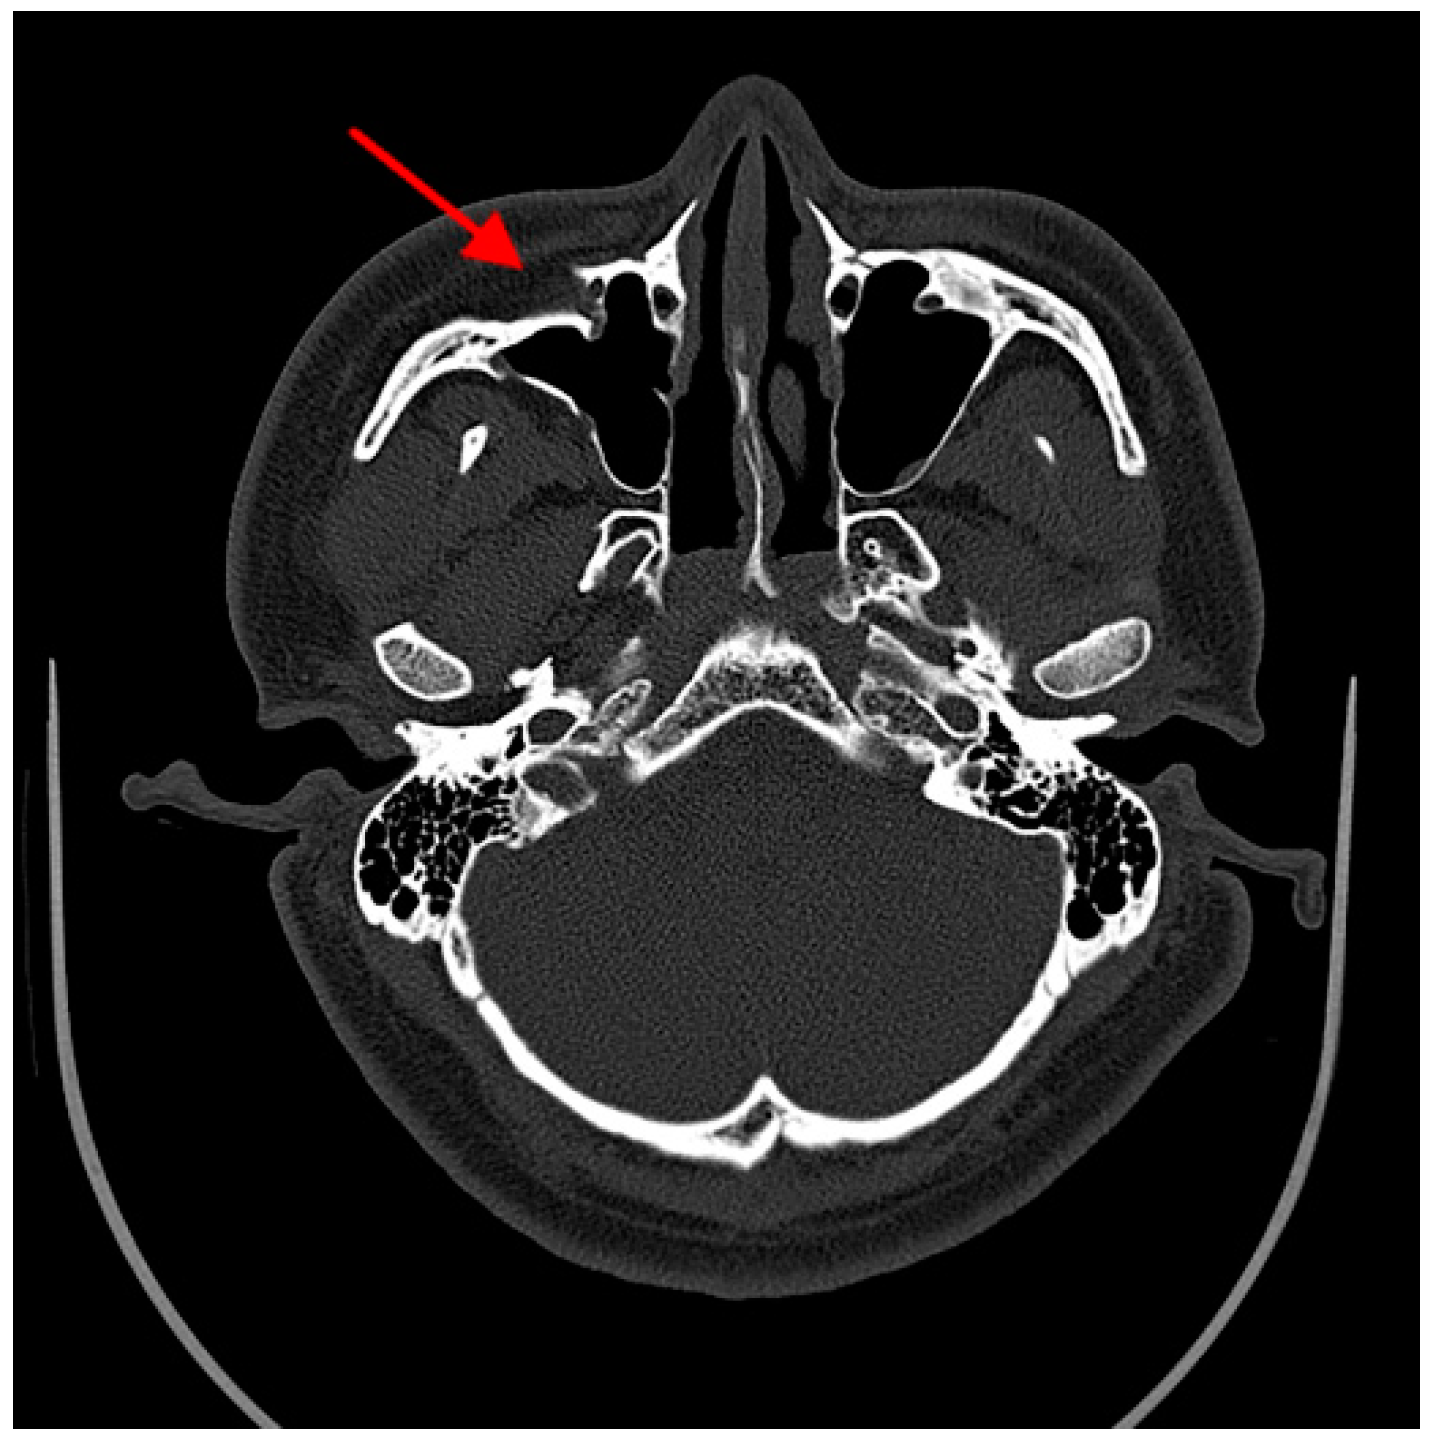

| Fracture reduction of maxillary sinus wall (X9) | |

| Perfect | 0 |

| Imperfect | 1 |

| Fracture reduction of maxillary sinus wall (sinus): | ||

| Perfect | 147 | 188 |

| Imperfect | 7 | 30 |